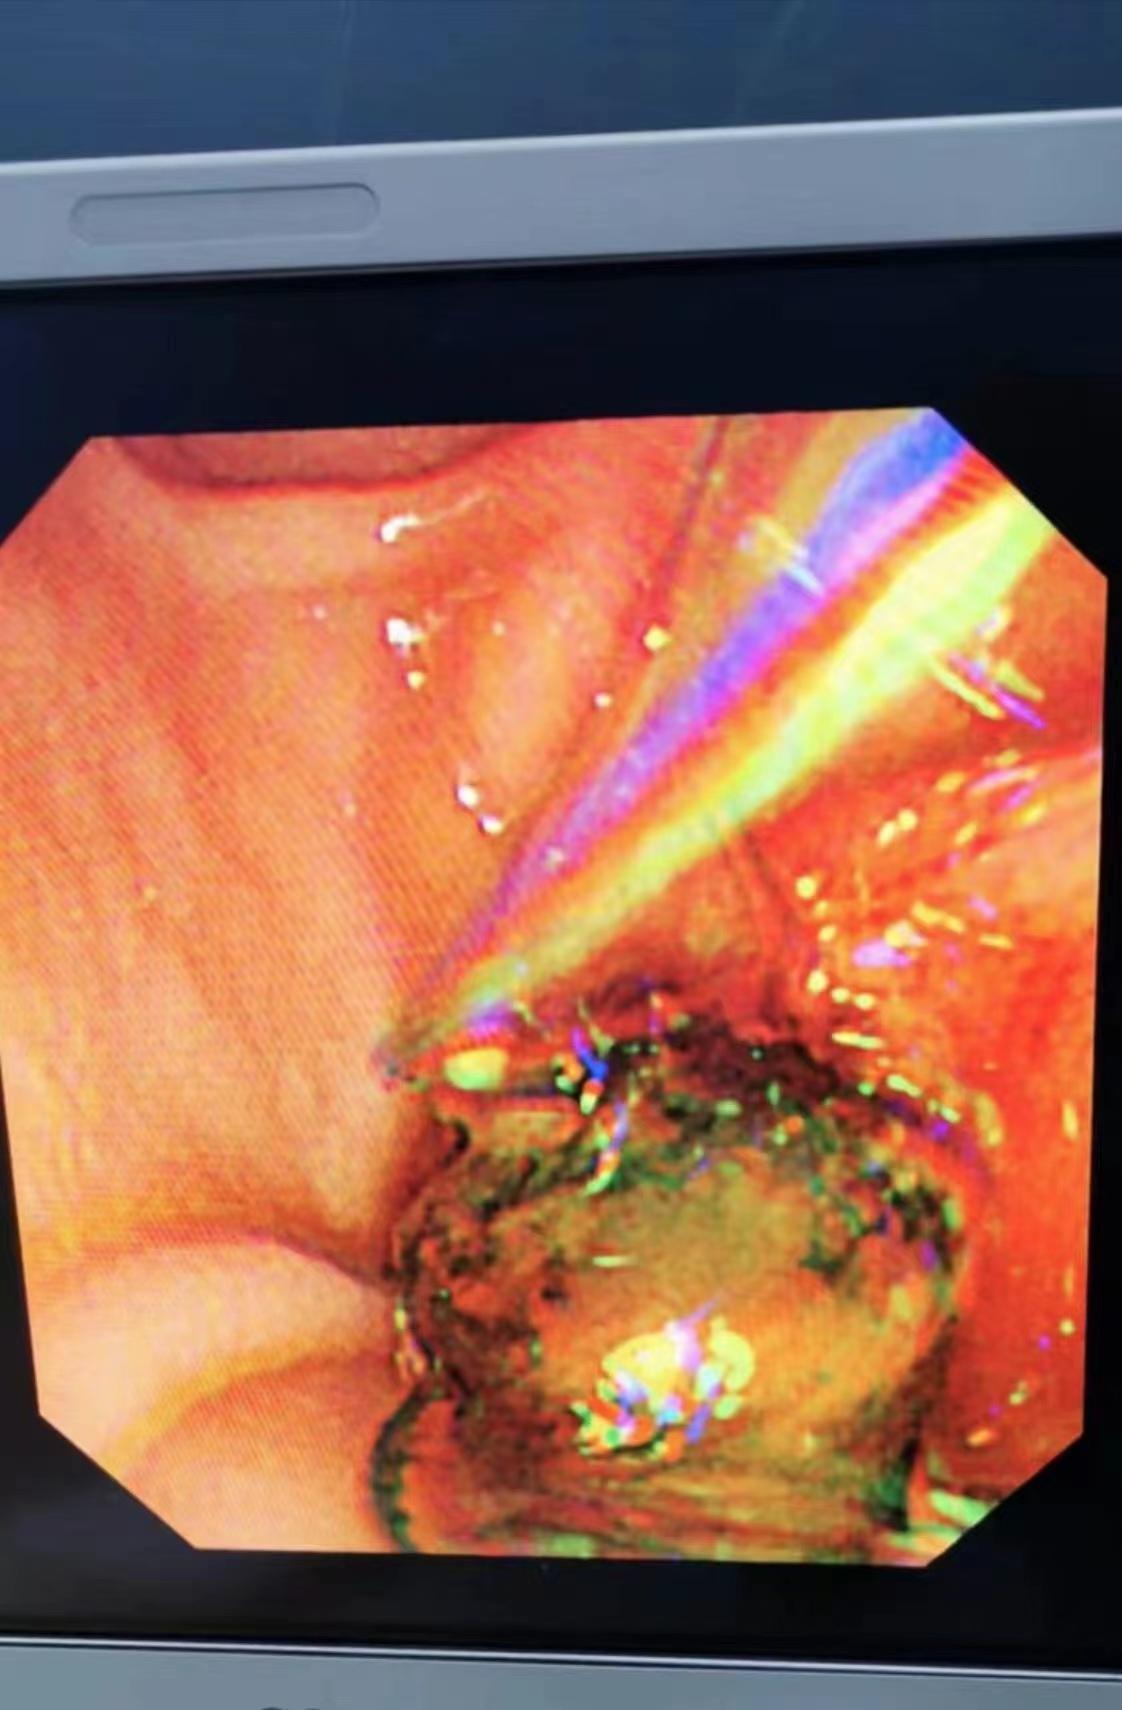

近期我院消化內(nèi)科于12月5日開展了一臺(tái)ERCP取石手術(shù),患者楊某某,女,40歲,因“全腹脹1月,尿色深、鞏膜黃染1周”入院,12月4日查肝功能示:ALT698.4u/l,AST278.7u/l,ALP448Iu/l,γ-GT1155Iu/l,總膽紅素22.6umol/l,直接膽紅素14.3umol/l,上腹部MRI+MRCP示:膽總管低信號(hào),考慮結(jié)石,經(jīng)全科討論后診斷、指針明確,擬行ERCP及相關(guān)技術(shù)取石治療, 術(shù)中過(guò)程通過(guò)進(jìn)境,插管,造影,乳頭擴(kuò)約肌切開,球囊擴(kuò)張,取石球囊、取石網(wǎng)籃取出結(jié)石,最后留置鼻膽管引流,術(shù)后患者未訴特殊不適,監(jiān)測(cè)生命征平穩(wěn),術(shù)后3h、12h及24h淀粉酶正常,術(shù)后24h復(fù)查肝功能:ALT233.4u/l,AST38.5u/l,ALP266Iu/l,γ-GT713Iu/l,12-9復(fù)查肝功能:ALT103.u/l,AST28u/l,ALP184Iu/l,γ-Gt477Iu/l,患者病情明顯好轉(zhuǎn),順利出院。